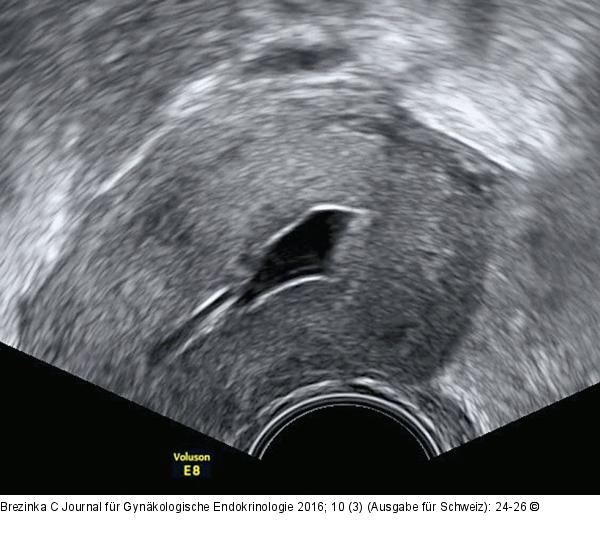

Abbildung 4: Ultraschall-Serometra HyCoSy, die iatrogene Serometra: Links im Bild ist deutlich der Katheter sichtbar, mit dem das echoarme NaCl ins Cavum uteri eingebracht wird. |

HyCoSy, die iatrogene Serometra: Links im Bild ist deutlich der Katheter sichtbar, mit dem das echoarme NaCl ins Cavum uteri eingebracht wird. |